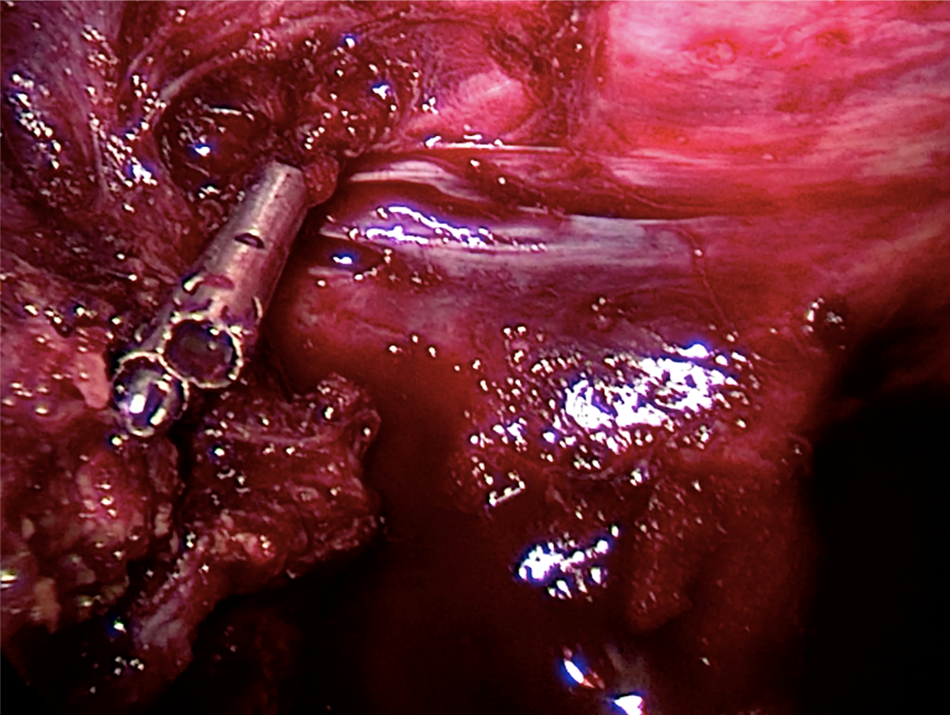

Open AccessCase Report

New Technique for Controlling Bleeding in Laparoscopic Liver Resection

Luigi Masoni, Leandro Landi, MD, Riccardo Maglio, MD

International Journal of Innovative Research in Medical Science·March 14, 2019